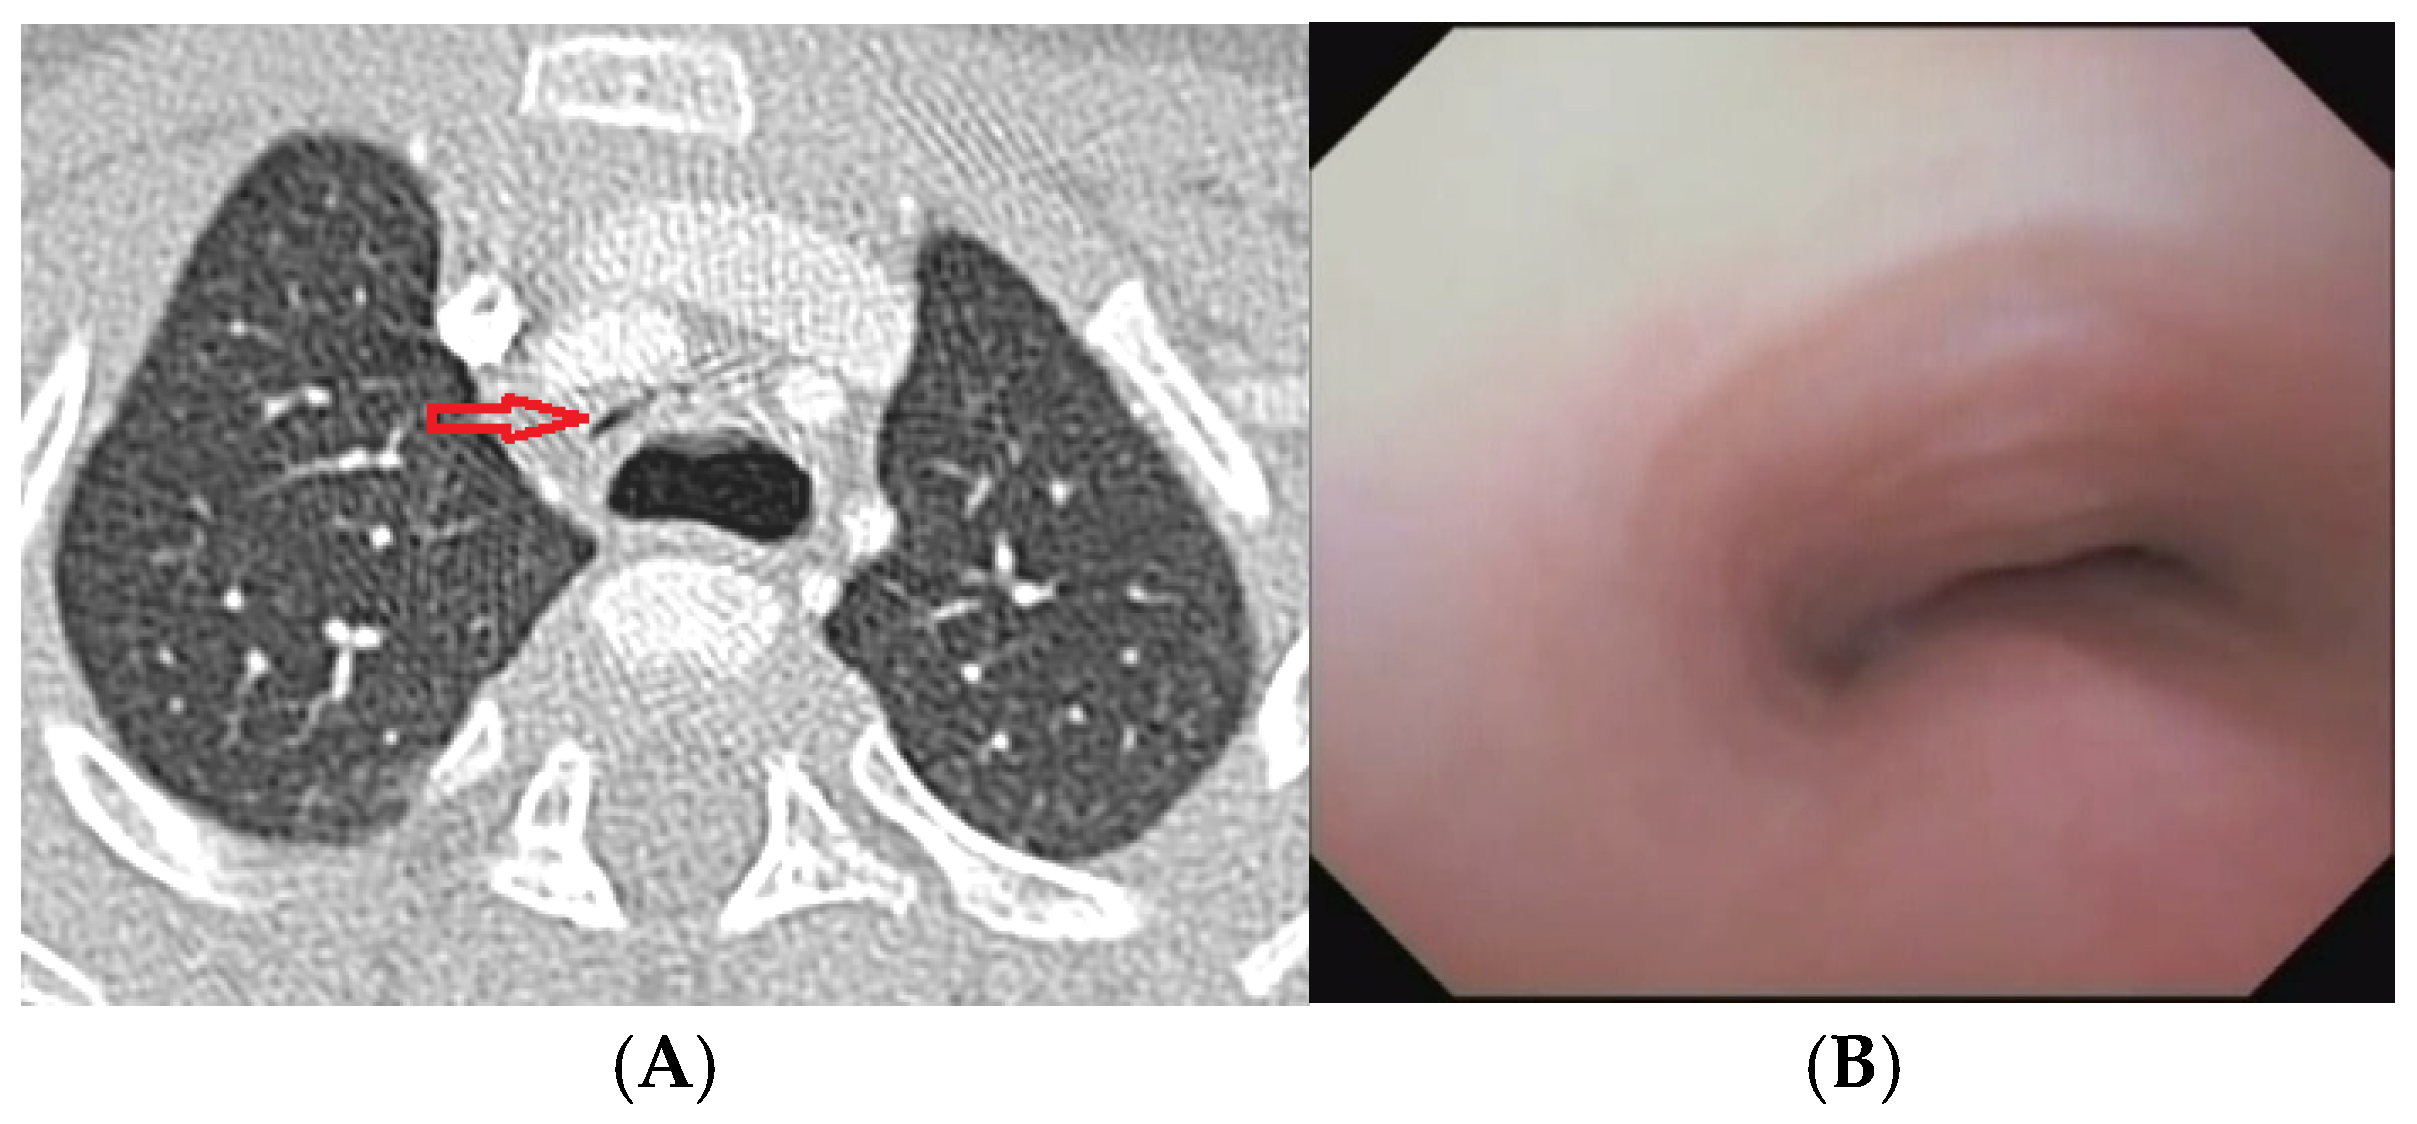

Figure 12.

A) Chest CT with CM: although the IA appears well pulled anteriorly towards the sternum, a severe TM is persistent with lumen occlusion > 75%, also because a large esophagus compresses the tracheal lumen from behind. B) The SVBS confirms the persistence of TM, with a patent but severely deformed tracheal lumen even in quit breathing. Abbreviations. CT: Computed Tomography; CM: Contrast Medium; IA: Innominate Artery; TM: Tracheo Malacia; SVBS: Static Videobronchoscopy.

After collegial discussion within the TT: PT was planned, which involves the partial displacement of the esophagus laterally to the right. After the surgery, there was a prompt clinical improvement with the disappearance of the recurrent biphasic cough. Endoscopy 6 months after the PT (